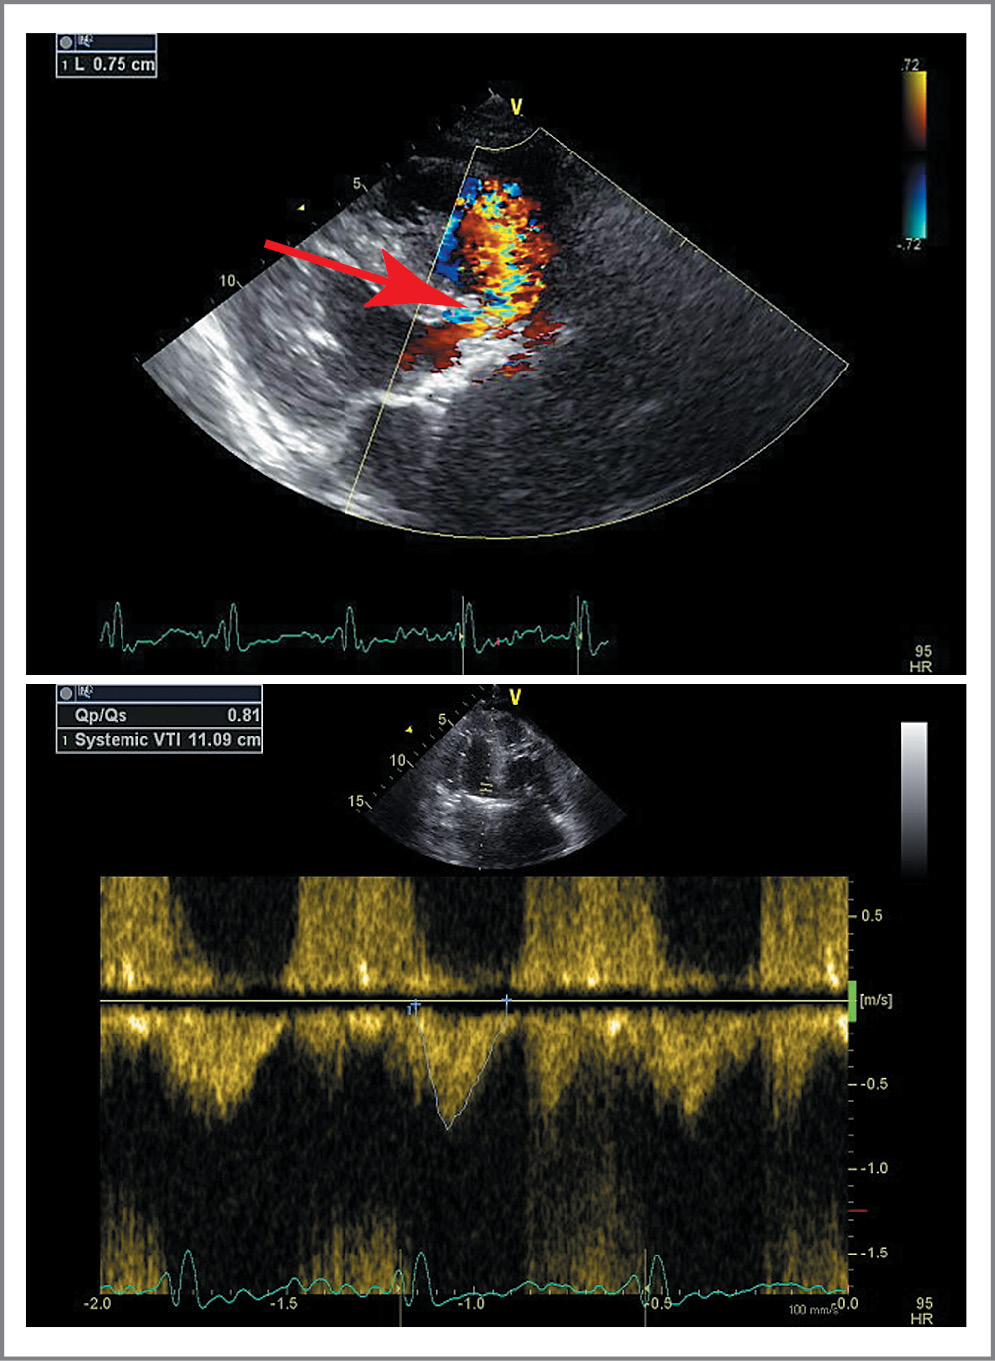

Рис. 2. ЭхоКГ при поступлении. Высокий дефект внутрижелудочковой перегородки (указан стрелкой) с определением соотношения легочного и системного кровотока.

Fig. 2. Echocardiography (EchoCG) on admission. High intraventricular septum defect (indicated by the arrow) with determining the ratio of pulmonary and systemic blood flow.

По данным эхокардиографии (ЭхоКГ): АС тяжелой степени – максимальная скорость 4 м/с, средний систолический градиент на АК 40 мм рт. ст., площадь раскрытия (планиметрически) 0,6 см2. Кальциноз АК 3-й степени. Аортальная недостаточность 2-й степени. Перимембранозный ДМЖП (диаметр около 7,5 мм) с двунаправленным сбросом крови, максимальный градиент давления между правым желудочком и ЛЖ – 50 мм рт. ст., соотношение легочного и системного кровотока QP/QS=0,8 (рис. 3). Высокая ЛГ (систолическое давление в ЛА – 103 мм рт. ст.), давление заклинивания ЛА – 19 мм рт. ст. Расширение обоих предсердий и правого желудочка (переднезадний размер 4,2 см), TAPSE – 0,9 см. Выраженная концентрическая гипертрофия миокарда ЛЖ (толщина МЖП – 1,5 см). Сократимость ЛЖ относительно удовлетворительная, фракция выброса – 57% (по Симпсону), конечно-диастолический размер ЛЖ – 4,4 см, ударный объем ЛЖ снижен (27 мл). В полости перикарда – до 120 мл жидкости. Признаки высокого центрального венозного давления.

По данным ЭхоКГ от 18.02.2019: в проекции АК визуализируется биологический протез типа CoreValve, амплитуда раскрытия створок в полном объеме. Регургитация АК 1->2 степени, парапротезная фистула со стороны передней створки митрального клапана. Выраженное нарушение региональной сократимости ЛЖ: определяется зона акинезии средневерхушечных сегментов со стороны всех стенок ЛЖ, гиперкинез базальных сегментов (рис. 6). Глобальная сократимость ЛЖ умеренно снижена, фракция выброса – 38–40% (по Симпсону). Сохраняется артериальная ЛГ, однако систолическое давление в ЛА снизилось до 80 мм рт. ст., т.е. стало меньше, чем при предыдущих исследованиях. Нижняя полая вена расширена, коллабирование ее снижено – признаки повышения центрального венозного давления. В области перимембранозной части МЖП определяется небольшой сброс крови слева направо (существенно меньше по сравнению с дооперационными данными – дефект частично прикрыт каркасом биопротеза). В полости перикарда патологического количества жидкости не выявлено.

Рис. 6. ЭхоКГ после операции. Акинез средневерхушечных сегментов ЛЖ: a – диастола; б – систола.

Fig. 6. EchoCG after surgery. Akinesis in the mid- and apical segments of left ventricle (LV): a – diastole; b – systole.